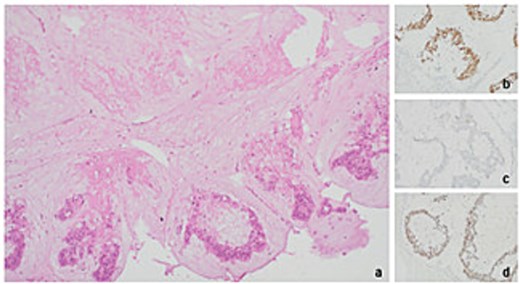

Histopathological analysis of the excised ileocolic mass showed mucinous adenocarcinoma, with serosal infiltration. Out of 22 lymph nodes, three were positive for metastases. Immunohistochemical analysis of mismatched repair genes showed microsatellite instability-low (MSI-L), with loss of MHS6 staining (Figs 3 and 4). Histopathology of axilla lymph nodes suggested metastatic mucinous adenocarcinoma (Fig. 4), with positive staining for CDX2 and SATB2 (Figs 5 and 6) in favour of malignancy of primary colorectal origin.

Immunohistochemistry (IHC) for mismatch repair proteins in right hemicolectomy sample at 20× magnification. (a) MLH1 retention in tissue (b) MSH2 retention in tissue. (c) MSH6 loss observed in tissue (d) PMS2 retention in tissue.